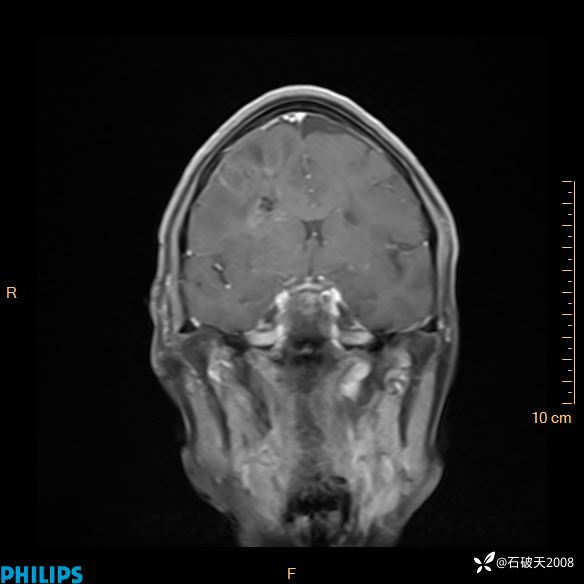

2024.2.21MR

增强冠状位